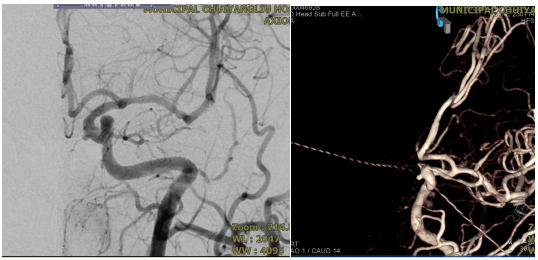

▲术前DSA

近日,清华大学附属垂杨柳医院神经内科成功为一名63岁女性患者拆除了脑内的“不定时炸弹”。该患者在住院期间通过脑血管检查,发现左侧颈内动脉C4段存在一枚动脉瘤。经综合评估,该动脉瘤破裂风险较高。

为精准把握手术指征与安全,术前,需完善全脑血管造影对动脉瘤的形态、大小及载瘤动脉的血管条件进行全面评估;术中,需由经验丰富的神经介入医生精准将密网支架植入病变部位;术后,患者需严格遵医嘱服用抗血小板药物,以预防支架内血栓形成及缺血性卒中事件的发生,并需定期复查全脑血管造影,以评估动脉瘤的最终闭塞情况。本例患者行密网支架植入术后三个月复查全脑血管造影,结果显示密网支架贴壁良好,无支架内血栓形成,继续用药和定期复查即可。